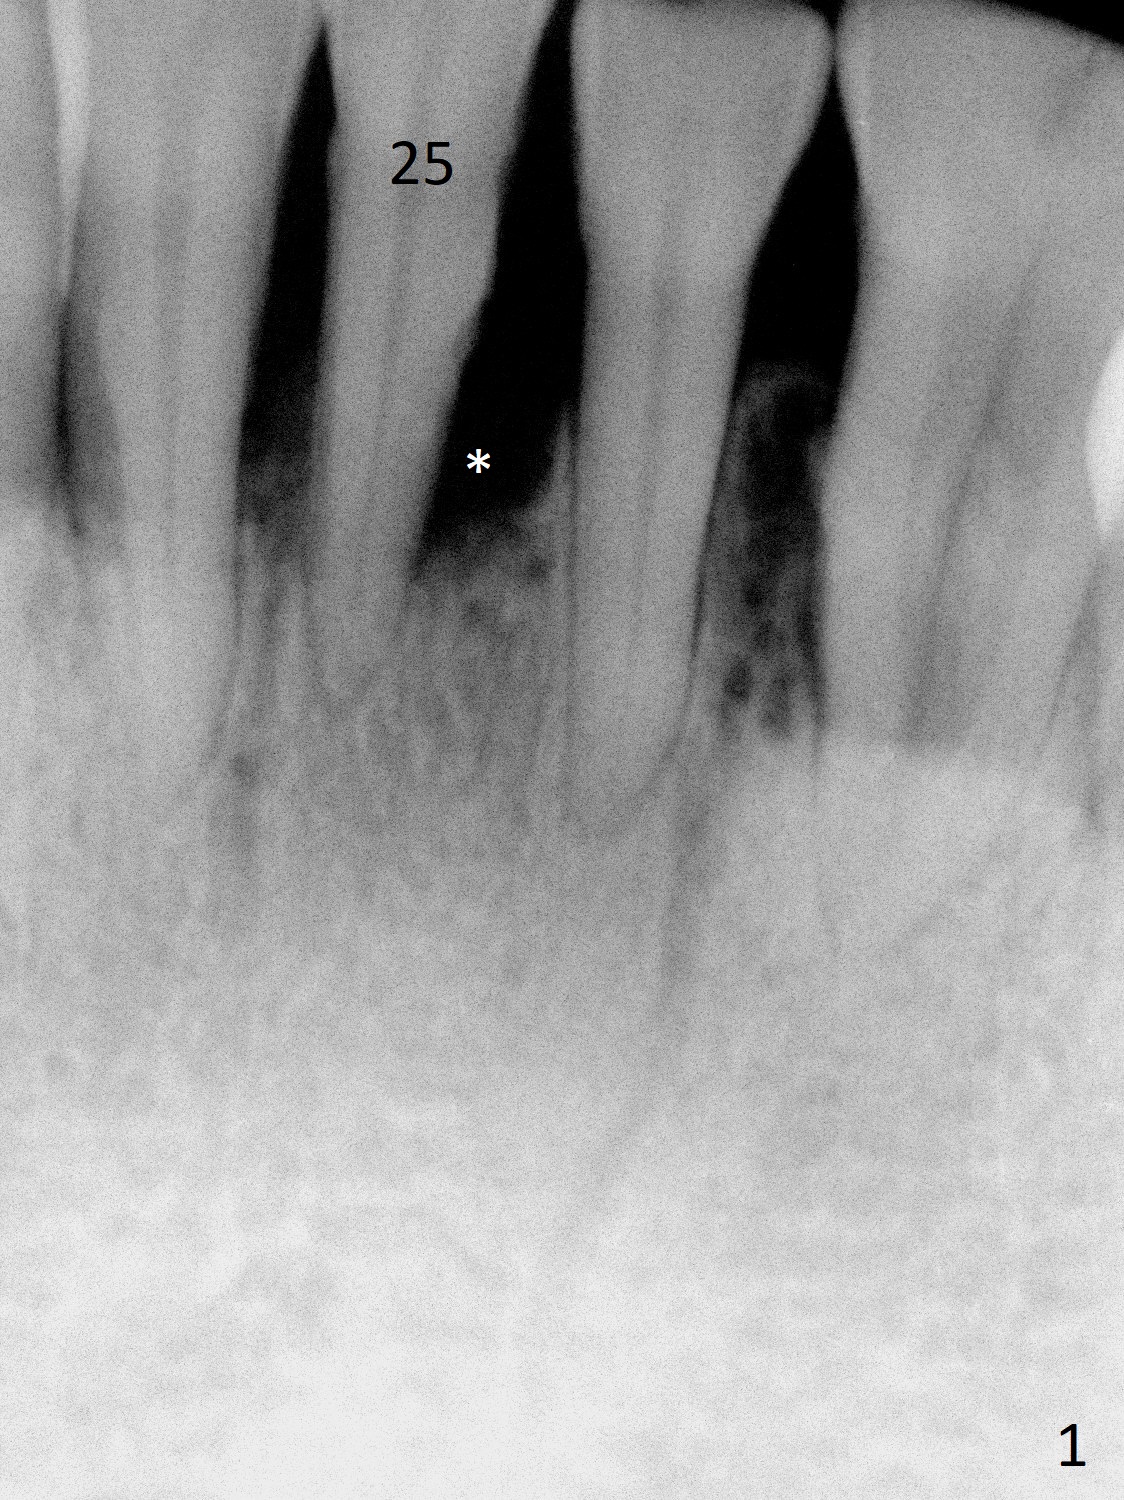

A 44-year-old woman has had bone loss at the tooth #25 for the last 4 years (Fig.1 *). Since the bone is narrow buccolingually (Fig.2 (CT coronal section)), a 1-piece implant with 2.5 mm in diameter is proper (Fig.3); but 12 mm in length makes the implant close to the lingual plate (Fig.2-4 L), with possible perforation. To avoid the latter, a shorter implant seems more appropriate for the site (Fig.5). Osteotomy is initiated in the apex with two fingers holding the buccolingual plates. Take PA preop. There is no buccal or lingual plate when the tooth is extracted; the socket bottom is flat buccolingually (Fig.6).